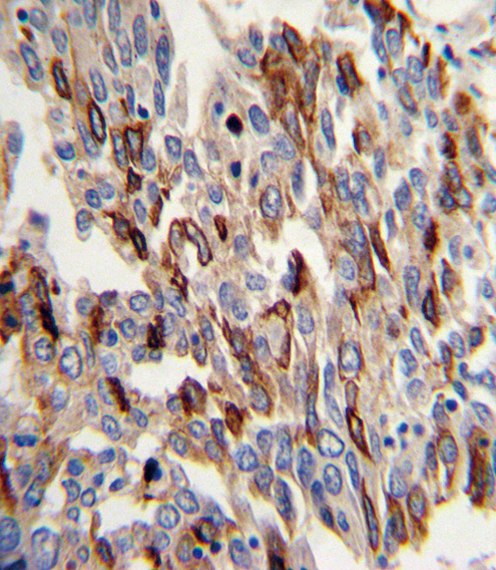

Formalin-fixed and paraffin-embedded human lung carcinoma with CD31 Antibody (C-term), which was peroxidase-conjugated to the secondary antibody, followed by DAB staining. This data demonstrates the use of this antibody for immunohistochemistry; clinical relevance has not been evaluated.